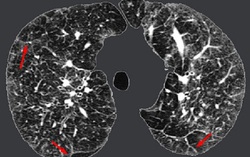

Phòng & chữa bệnh 16:03 12/03/2020Mới đây, nữ bệnh nhân số 17 bị nhiễm virus corona chủng mới (Covid-19) trong quá trình điều trị có biểu hiện viêm phổi kẽ. Tuy nhiên, nhiều người lo lắng bởi không biết viêm phổi kẽ là bệnh như thế nào, biểu hiện, cách phòng tránh ra sao?